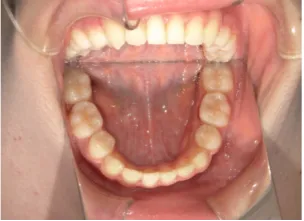

治療前①小2:8y1m 初診

治療中➁小3:9y8m QH、BH、前歯並び替え終了

治療後⑩高2:17y7m 抜歯治療終了

| カウンセリング・診断結果 | 前歯が受け口になっていているため、適正な成長へ誘導するために前歯の咬み合わせの改善が必要なことを説明し、診断を希望されたので精密検査へ進みました。 精密検査の結果、骨格的には受け口傾向、下顎前歯の突出、上下ともアーチが小さく凸凹(叢生)が認められ、機能的には低位舌と口唇閉鎖不全があり、口元は上下唇とも突出していますがコンケーブになってないことがわかりました。 |